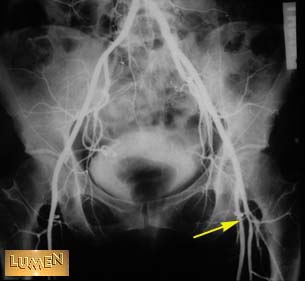

Question: Identify.

Femoral artery.